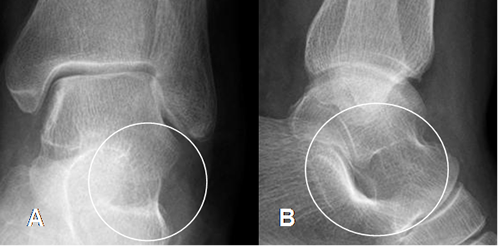

Fig 105. Seno del tarso normal.

A: Rx AP y B: Rx lateral. Espacio normal en la parte lateral.